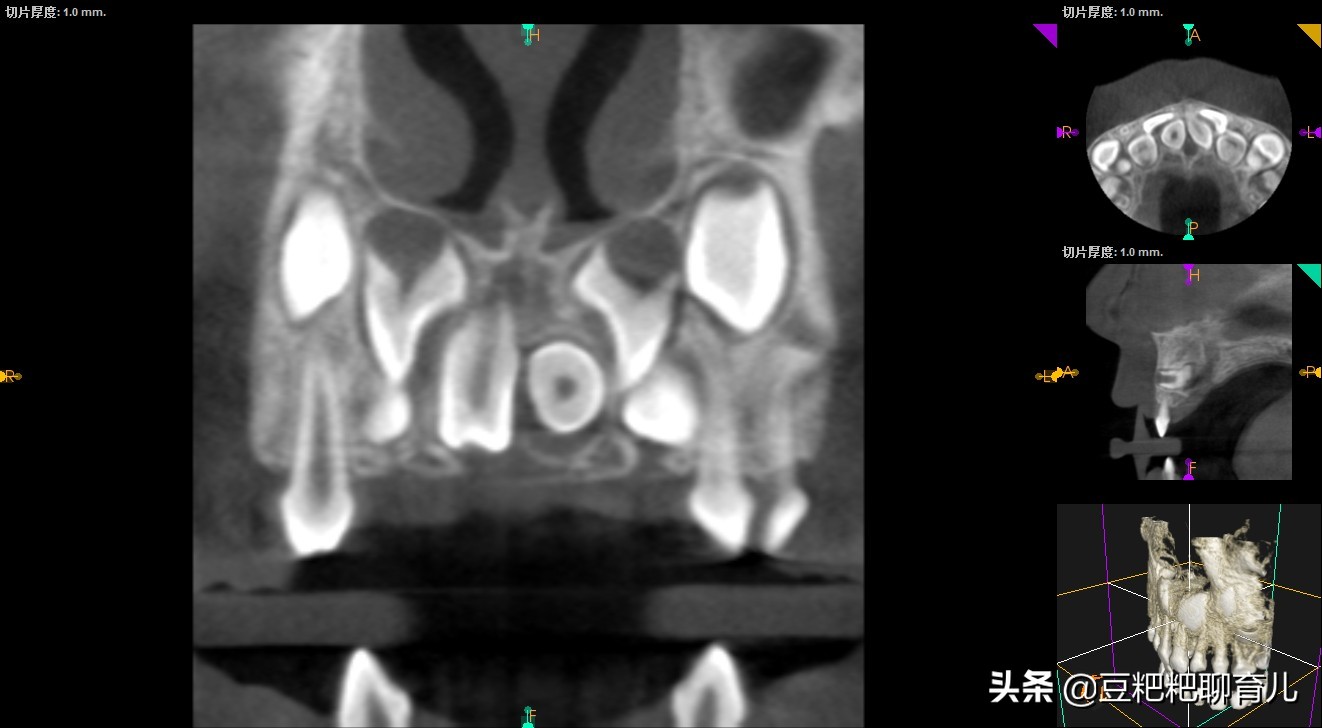

我儿子的就是"埋伏性正中多生牙",就是从表面看不见生长在牙龈里面,需要照X光才能发现。而且一颗是正常生长的,一颗是横着长的。